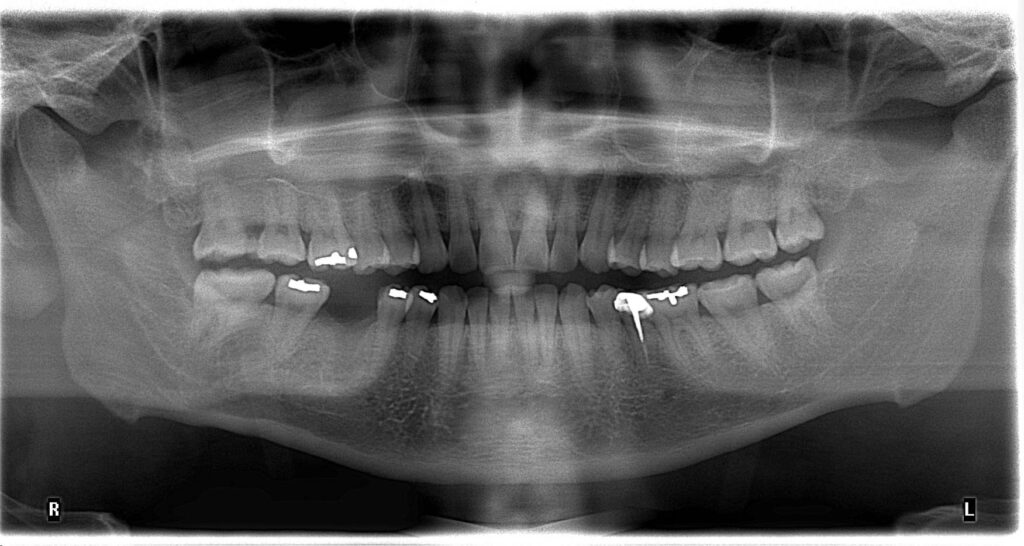

一開始只是單純的根管治療,

沒想到過程中發生器械分離的併發症,

導致牙根受損,最終只能走向拔牙 → 改做植牙 😵💫